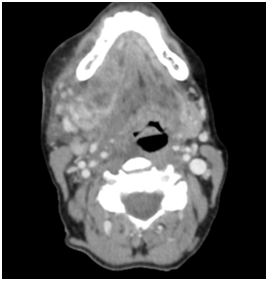

The patient was admitted to intensive care and electively extubated the next day after demonstration of a cuff leak and further fibreoptic examination by the otolaryngology team. Following successful extubation, the patient was transferred to the ward to continue intravenous antibiotics and observation. The patient was discharged six days later with oral antibiotics and cessation of immunosuppression medication until follow up in six weeks by the respiratory team regarding the apical lung abscesses (Figure 1).

Figure 1 Axial slice computed tomography demonstrating a large collection displacing the oropharynx to the left.

A 67 year old lady presented to Torbay Hospital, a district general hospital, three days following the extraction of her lower right wisdom tooth with swelling and pain of her right jaw and neck, swelling of her tongue and difficulty swallowing. Medical history included rheumatoid arthritis managed with hydroxychloroquine and methotrexate. Examination revealed significant submandibular swelling extending to the submental region, and erythema extending to her sternal notch. Mouth opening was reduced to 15mm, Mallampati score was 3 and neck extension was significantly limited due to the sizeable right sided neck swelling and pain and her underlying rheumatoid arthritis. In spite of these findings, she was physiologically more stable than expected. Computed tomography of the neck demonstrated a right submandibular, buccal and sublingual collection extending to the right parapharyngeal, carotid, retropharyngeal and prevertebral spaces. This had resulted in displacement of the oropharynx to the left and narrowing of the airway superiorly. Infection had extended so far as to cause apical lung abscesses and had led to a right internal jugular thrombosis.